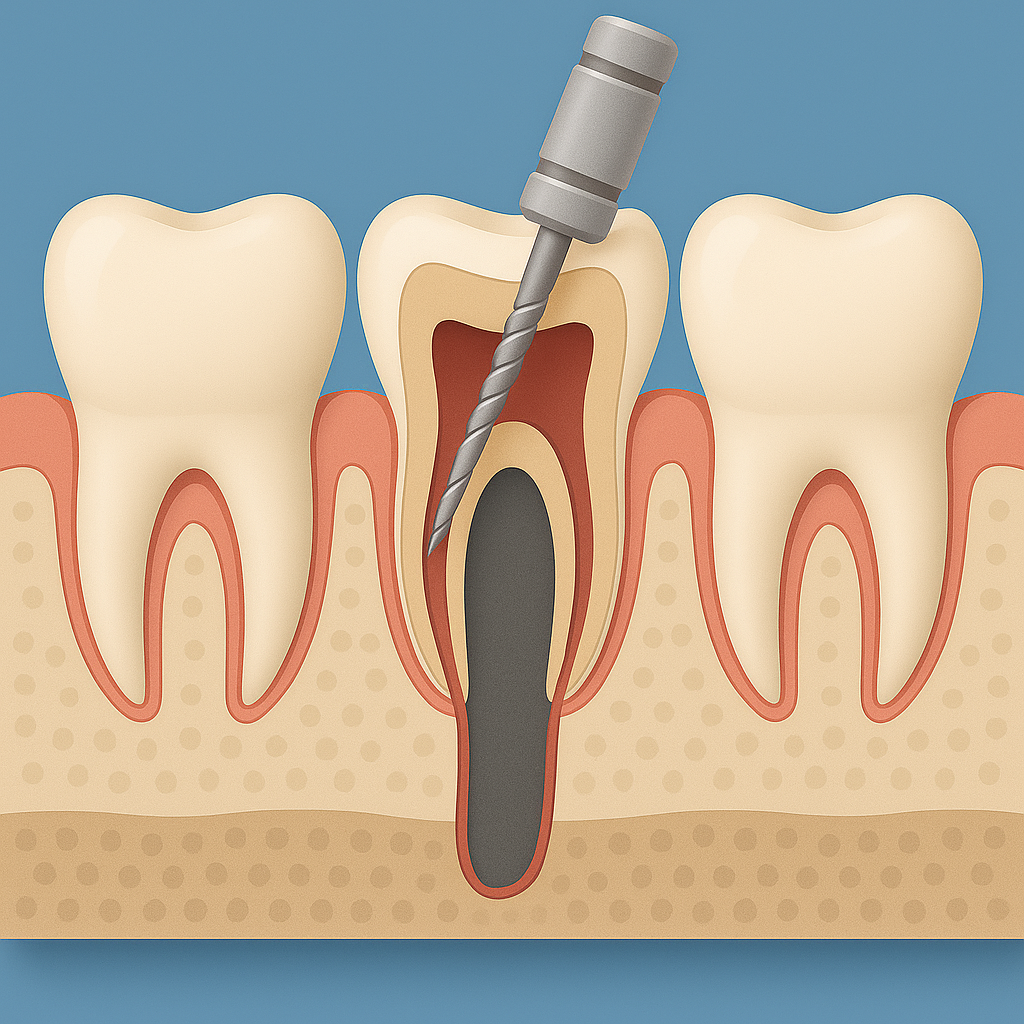

Çürük Diş Kanal Tedavisi İşlemi Nasıl Yapılır?

Çürük dişte yapılan kanal tedavisinin amacı, iltihaplanan siniri temizleyip dişi çekmeden sağlıklı hâle getirmektir. Önce muayene ve röntgenle dişin durumu değerlendirilir, ardından lokal anestezi ile bölge uyuşturulur. İnce aletlerle kök kanalları içindeki mikrop ve dokular temizlenir, kanallar dezenfekte edilip şekillendirilir. Sonrasında bu boşluklar özel dolgu maddeleriyle sıkıca kapatılır; gerekiyorsa dişin üzerine dolgu ya da kaplama yapılır. Böylece ağrı kaybolur ve dişiniz çiğneme sırasında yeniden güvenle kullanılabilir.

Kanal Tedavisi Aşamaları

Röntgen kontrolü

Lokal anestezi

Lastik örtü yerleştirme

Erişim deliği açma

Kanal törpüleme

Mikro kalıntı temizliği

Delik kapatma